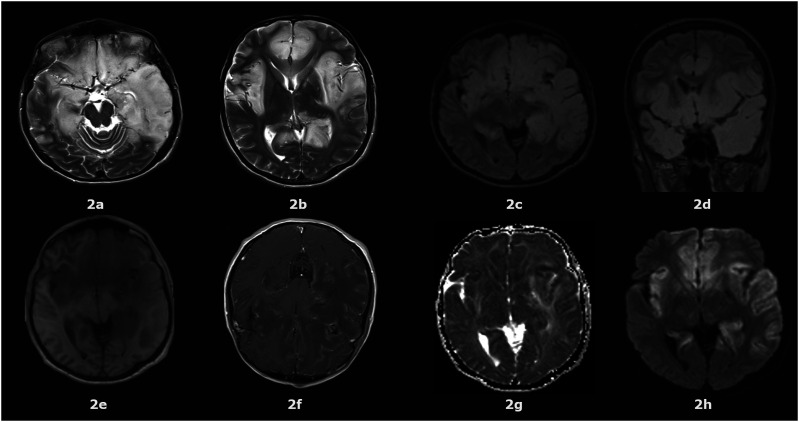

Abstract Image